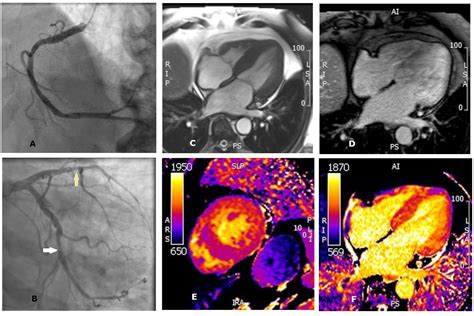

Transient Ischemic Dilation is defined as the apparent increase in the size of the left ventricular (LV) cavity on post-stress MPI images compared to rest images. This phenomenon is typically observed in patients undergoing either exercise or pharmacological stress testing. While the heart muscle does not actually change size in such a short window, the visual "stretching" or dilation effect is a surrogate marker for extensive, multi-vessel myocardial ischemia or severe left main coronary artery disease.

When the heart is subjected to stress, restricted blood flow in multiple coronary arteries leads to a widespread reduction in myocardial uptake of the radiotracer. This global subendocardial ischemia results in the apparent widening of the LV cavity when the stress images are compared to the rest images, where perfusion might appear more uniform. Recognizing Transient Ischemic Dilation is therefore a vital skill for cardiologists and radiologists, as it flags patients who are at a significantly higher risk for major adverse cardiac events.

1. Coronary Angiography: Invasive visualization of the coronary arteries to determine the exact degree of stenosis.

With the advent of PET (Positron Emission Tomography) and improved SPECT reconstruction algorithms, the accuracy of detecting Transient Ischemic Dilation continues to improve. Newer technologies allow for better attenuation correction and higher image resolution, which helps in distinguishing between true ischemia-driven dilation and technical noise. These advancements ensure that the sensitivity of MPI remains competitive against more invasive diagnostic modalities.